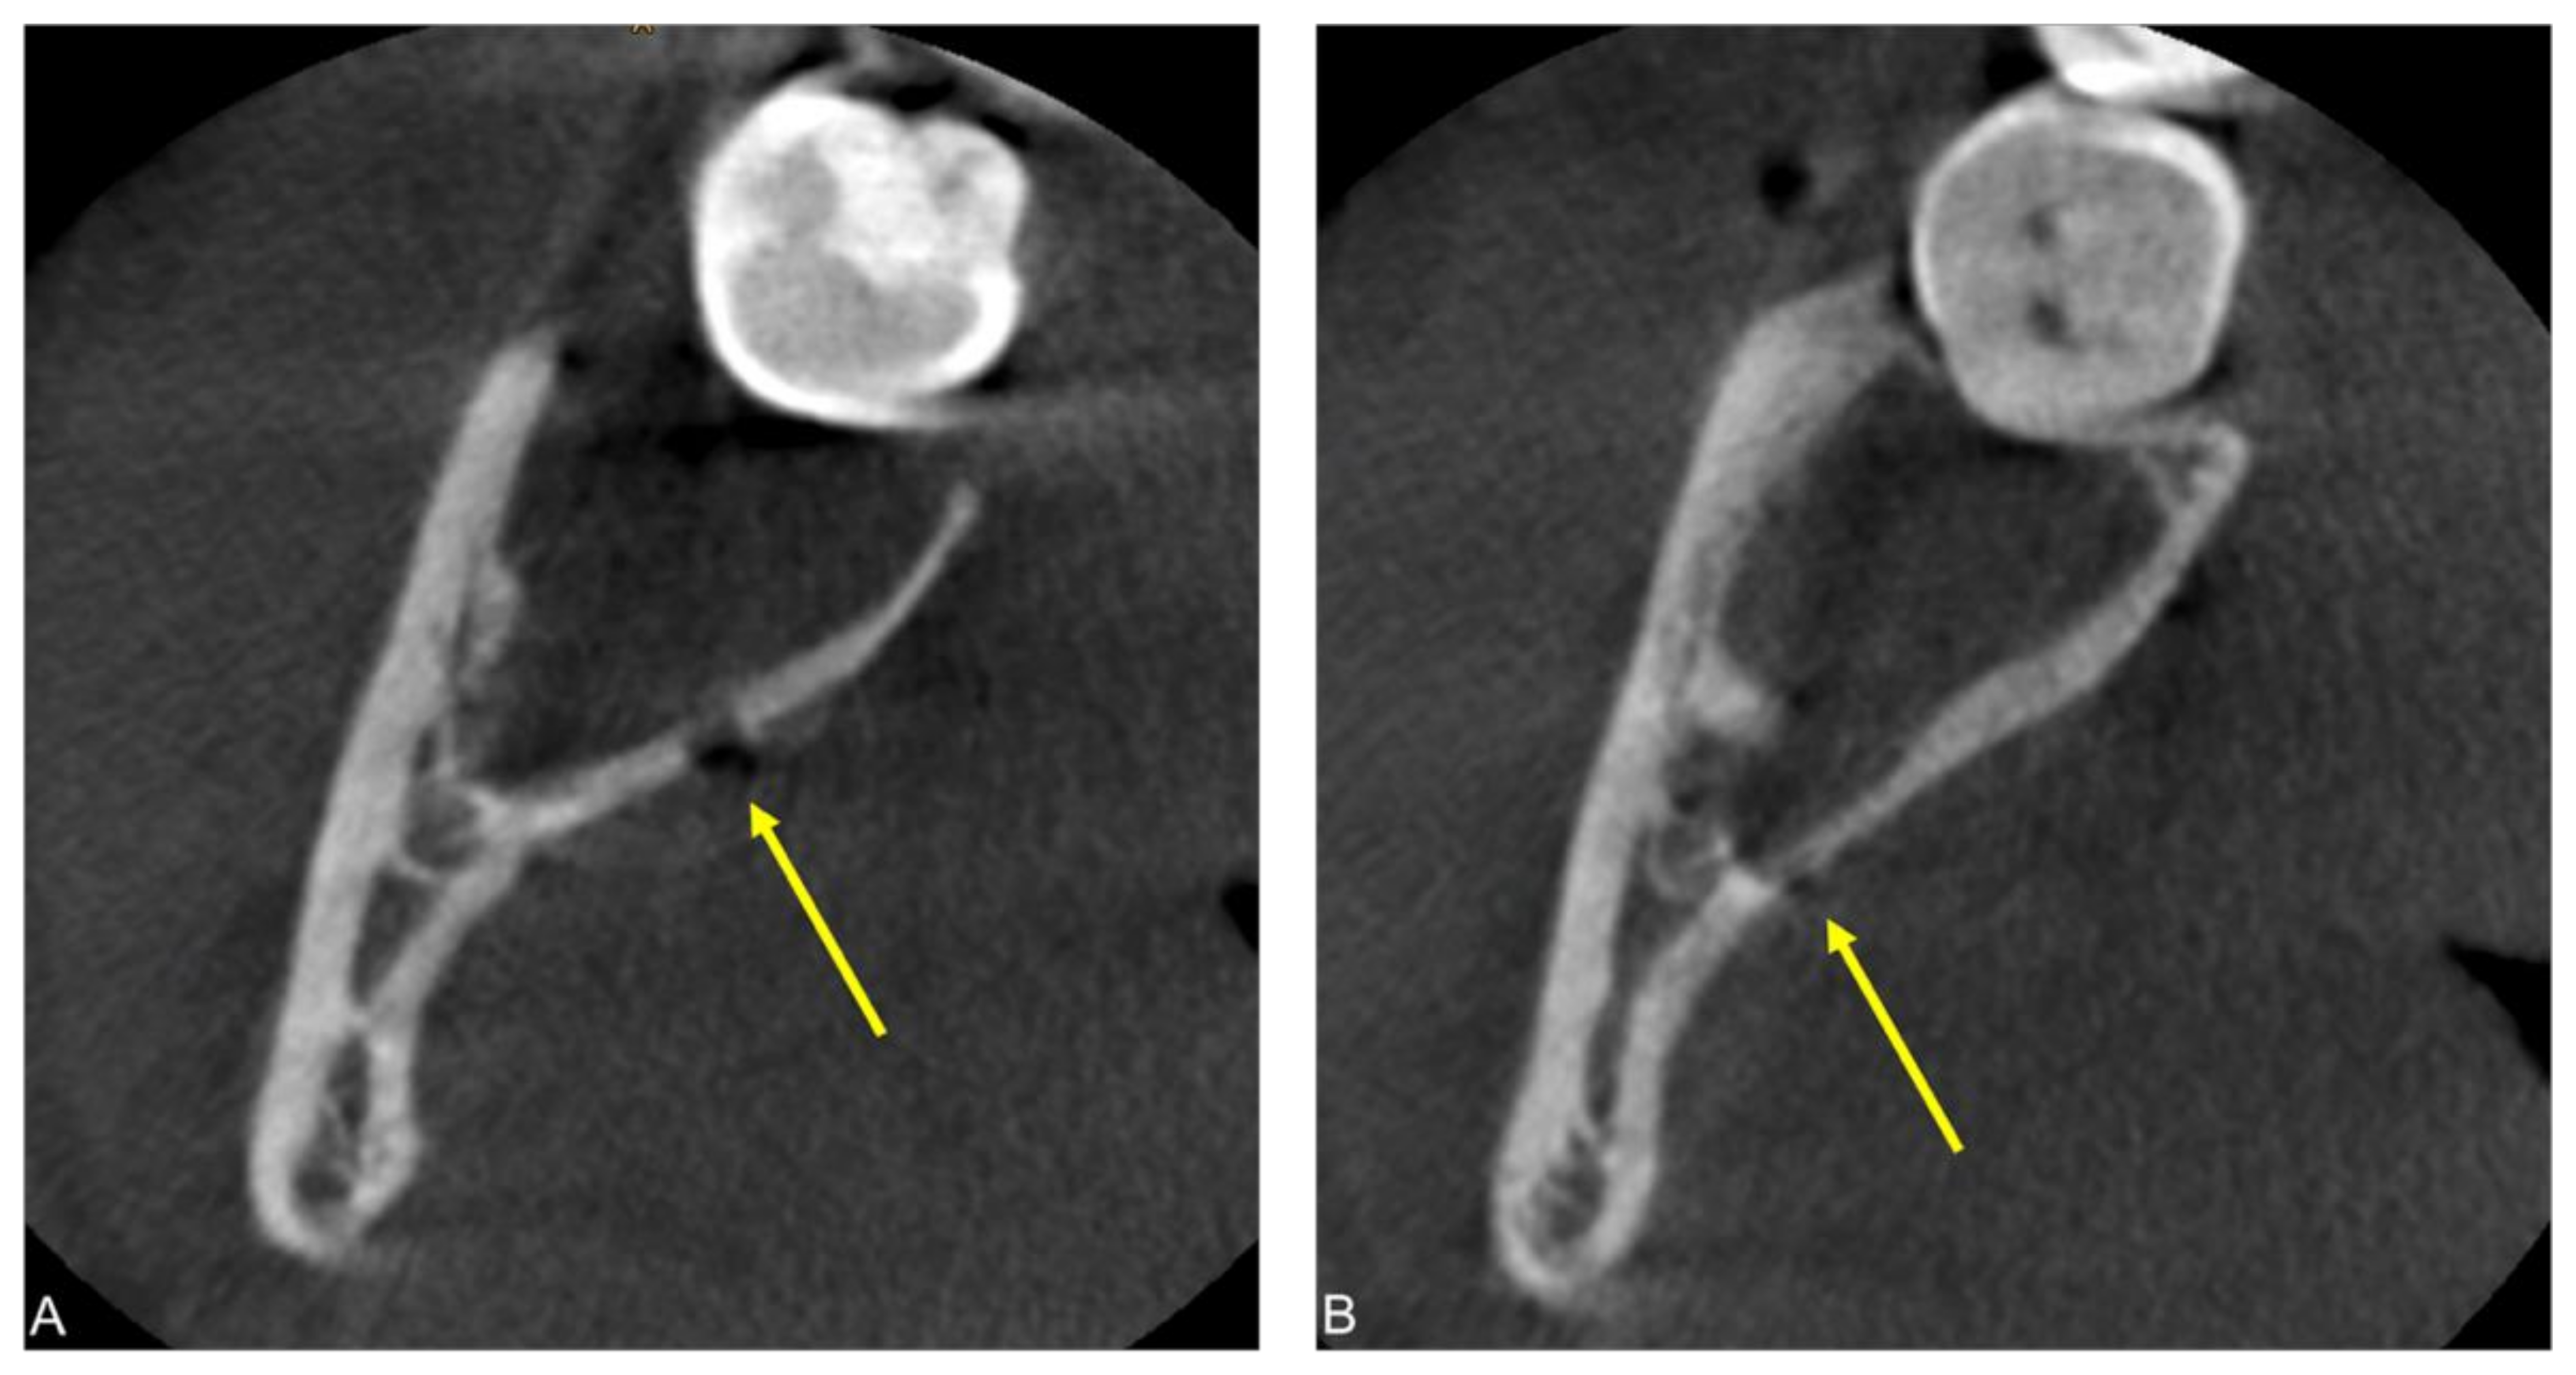

2.1. Case 1

2.2. Case 2